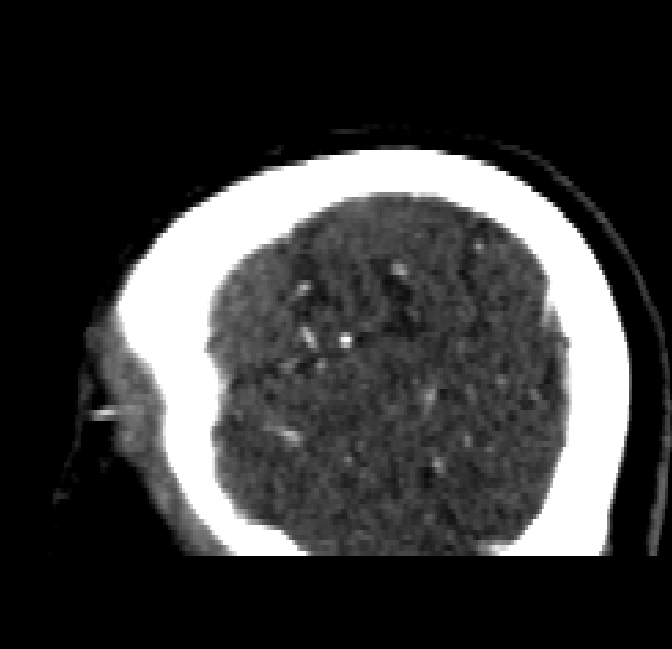

After fine-tuning, the two pre-train conditions appear to have little or no difference in terms of qualitative performance at the vessel segmentation task. However, when compared to the models trained only on real data, there are noticeable differences. Throughout Figures 4.3-4.9, the model pre-trained on scans with original CT noise is to be taken as representative of segmentation performed by the Perlin noise pre-training condition. Images showing the hand-labeled ground truth, as well as the unlabeled slice, are presented for comparison.

Figure 4.8: Side view of segmentations on regions near the left side of the skull. Unaltered image (left). No pretrain model (mid-left). Fine-tuned model (mid-right). Hand-labeled ground truth (right).

The models appear to have a hard time segmenting vessels close to the skull surface. The model trained exclusively on patient data appears to struggle far more for these types on conditions than the fine-tuned models. Figure 4.8 shows an example of the fine-tuneds model having close to no trouble segmenting vessels near the left side of the skull, while the baseline model suffers heavily from false negatives. To lesser degree, this effect can also be observed in the frontal lobe of Figure 4.9 In the other hand, Figure 4.7 presents an example of both models failing to segment vessels near the top of the skull.